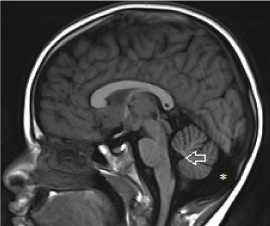

Figure 9. Axial T2-weighted image shows marked ventriculomegaly without subarachnoid space enlargement in a patient with communicating hydrocephalus. This child exhibits signs of raised intracranial pressure on physical examination.

A positive “cortical vein sign”, defined as visualization of bridging cortical veins within the enlarged subarachnoid spaces, assists the radiologist in differentiating external hydrocephalus from subdural fluid collection [37] (Figure 7,8). Cerebral atrophy with ex-vacuo ventriculomegaly can be differentiated from external hydrocephalus as there is often global enlargement of subarachnoid spaces, in contrast to frontal predominance in external hydrocephalus. There is also absence of macrocephaly. Communicating hydrocephalus will display clinical evidence of raised intracranial pressure [38] and is often associated with sulcal effacement rather than subarachnoid space enlargement (Figure 9). It is important to differentiate communicating hydrocephalus from ex-vacuo ventricular dilation as the prior may pose damage to the developing brain. The decision for therapeutic intervention is often based on the demonstration of progressive increase in ventricular dimensions on serial imaging [39]. One must be aware that there is often a small progressive increase in size of the anterior horn width in both term and preterm neonates in the first week and life and this physiological change should not be interpreted as progressive ventriculomegaly [40,41,42,43].